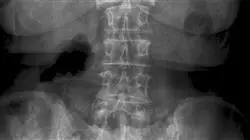

1.1.1. Imágenes en las fracturas toraco-lumbares y sacro

1.1.1.3. Manejo y uso de las imágenes radiológicas

1.1.1.4. Definir las indicaciones del Uso apropiado del TAC o RMN